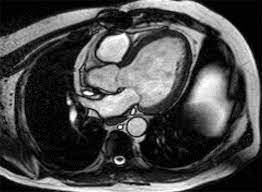

Cardiac MRI is a non-invasive imaging technique that provides detailed pictures of the heart's structure and function. It is particularly useful in diagnosing complex cardiac conditions that might not be visible through other diagnostic methods. For Rajesh, this modern marvel was a game-changer.

The results of the cardiac MRI were illuminating. It revealed that Rajesh had a condition known as myocardial ischemia, which was causing reduced blood flow to his heart. Armed with this knowledge, Dr. Desai was able to create a tailored treatment plan that included medication and lifestyle changes.